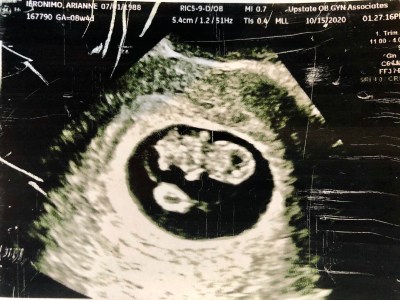

After work, we went out to a family dinner to celebrate my stepson’s birthday. At least that’s why I though we went to dinner. It turned out that it was to tell us that we’re going to be GRANDPARENTS!!

Thanks. Can’t wait until May.